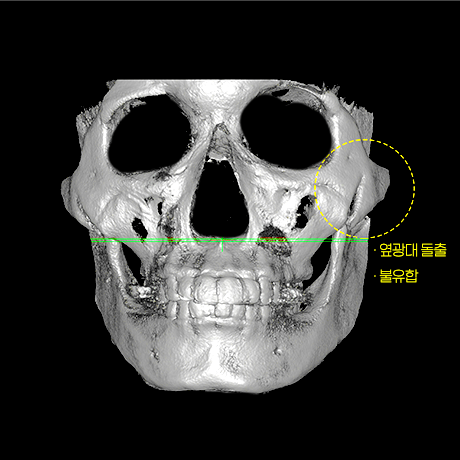

아이디병원의 윤곽 재수술은 광대의 가장 튀어나온 부분인

‘MMP’를 하이엘 절골/축소 방법으로 과도한 절제 없이 광대를 최대 축소하며,

첫 수술 후 45° 광대가 크고

좌우 비대칭 심함

옆 광대뼈 벌어짐 있음